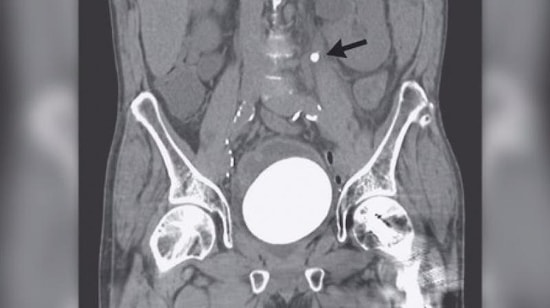

İdrar yolları enfeksiyonu mesaneyi, böbrekleri, üreteri (idrar yolunu) etkileyebilen yaygın bir enfeksiyondur. Belirtiler arasındaki en yaygın olanları ise çişinizi yaparken kaşıntı ve sızlama hissi, sık sık tuvalete gitme ihtiyacı, bulanık renkte idrar ve bulantı hissidir. İnternette bu konu ile ilgili bir sürü efsane dolaşıyor. İdrar yolu enfeksiyonundan kurtulmanın yolları mevcut. Tedavisi var. Bitkisel tedavilerden tutun da antibiyotiklere, ilaçlara kadar pek çok çözüm önerisi var. İdrar yolu iltihabına ne iyi gelir, evde basit uygulamalarla nasıl çözümler üretebilirsiniz hep birlikte direkt konuya girelim. Erkeklerde ve kadınlarda da idrar yolları enfeksiyonu görülmektedir. King College Hastanesi'nden ürojinekoloji profesörü Linda Cardozo ve kadın hastalıkları ve doğum konusunda uzman Royal College sözcüsü bu konuya bir açıklama getirmek için soruları yanıtladı.